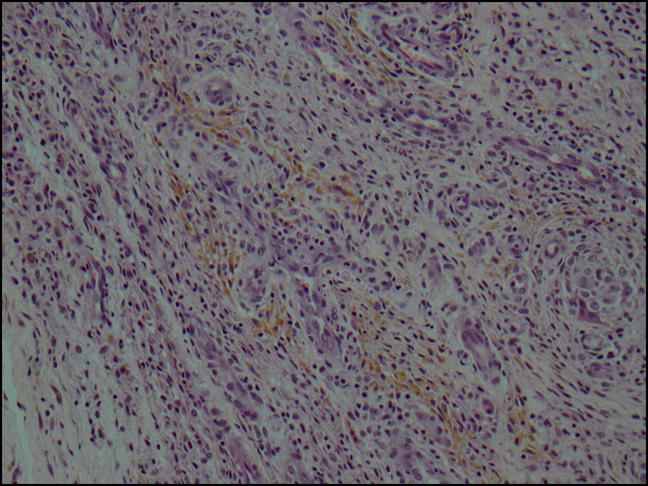

Tenosynovial giant-cell tumor (TGCT) is an intraarticular giant-cell tumor of the synovial tissue and tendon sheaths which often mimics multiple conditions on presentation. This case report describes a previously asymptomatic 67-year-old man with preliminary clinical and laboratory evaluation suggestive of septic arthritis; however, arthroscopy revealed diffuse synovitis, and biopsy confirmed TGCT. To our knowledge, this is the first report of TGCT presenting as septic arthritis in an adult patient. This diagnosis should be considered in evaluation of acute, atraumatic knee pain with associated inflammatory marker elevation.

腱鞘巨细胞瘤(TGCT)是一种发生于滑膜组织和腱鞘的关节内巨细胞瘤,其在发病时常表现为多种类似的病症。本病例报告描述了一例此前无症状的 67 岁男性,初步的临床和实验室评估提示为化脓性关节炎;然而,关节镜检查显示弥漫性滑膜炎,活检证实为 TGCT。据我们所知,这是首例成人 TGCT 表现为化脓性关节炎的病例报告。在评估伴有炎症标志物升高的急性、非创伤性膝关节疼痛时,应考虑到这一诊断。